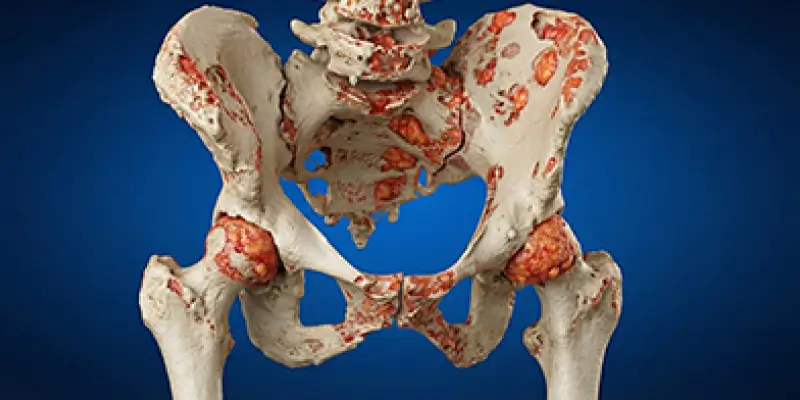

Kemik metastazı, başka organlardan kemiğe yayılan kanserin neden olduğu ciddi bir durumdur. Belirtileri, teşhisi, tedavi yöntemleri ve ağrı yönetimi.

Başka organdan kemiğe sıçrayan kanserlerde (metastaz) kırık riskini önleyen cerrahiler ve ağrı yönetimi. Ortopedik onkolojide metastaz yaklaşımı.